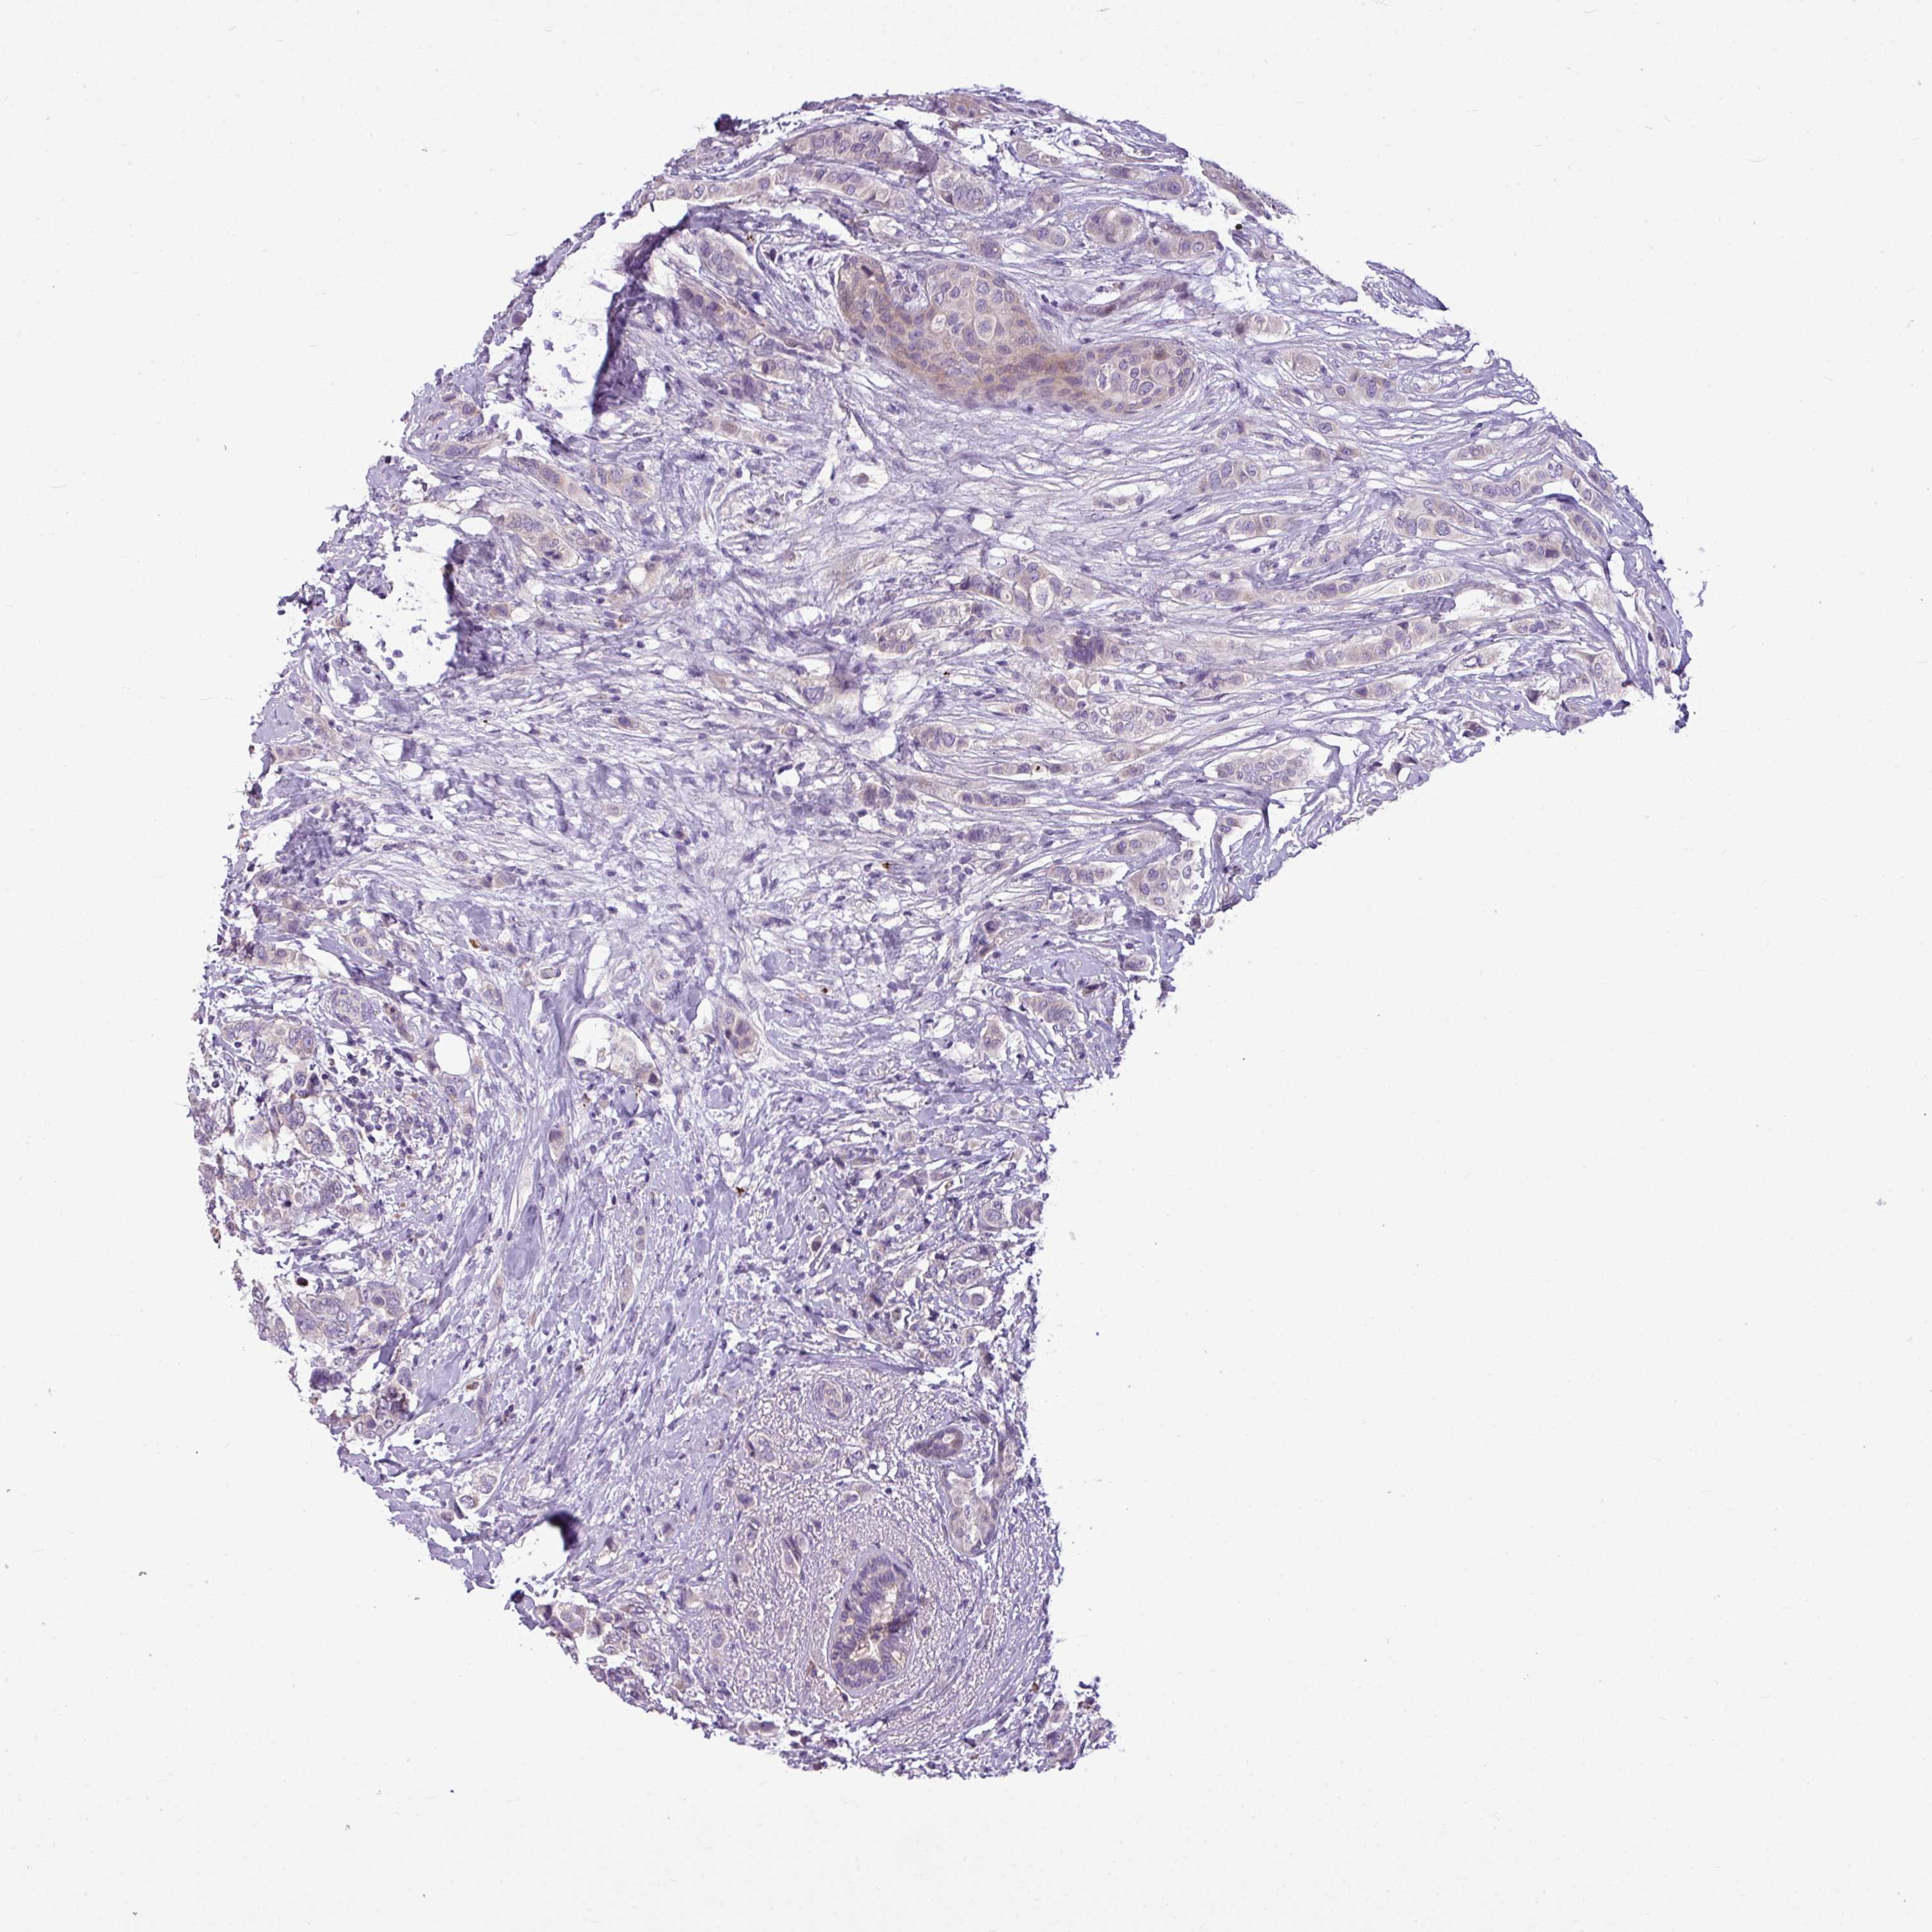

BRCA TCGA BRCA VALIDATION PROTEIN EXPRESSION

Breast cancer

Human cancer

Breast invasive carcinoma